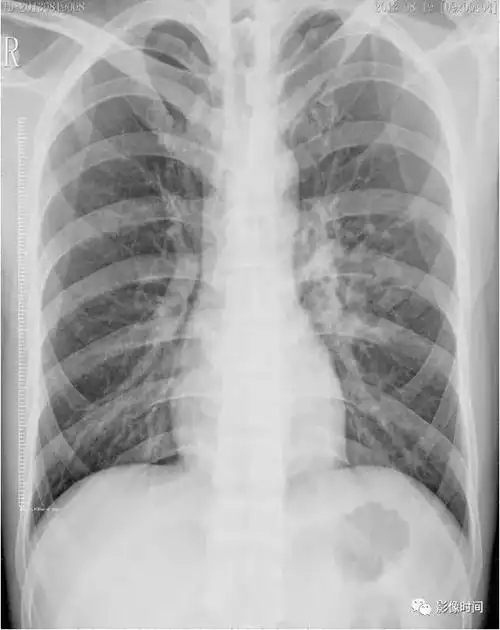

支原体肺炎影像分析

(a) 最初的胸片显示两个下肺区,尤其是左心后区,边界不清的结节影